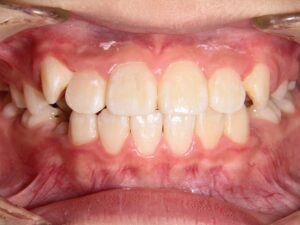

第1期治療開始時

顔貌写真

口腔内写真

年齢

9歳 男性

主訴(患者様のお悩み)

歯のデコボコを治したい

診断

上顎前歯部叢生(上の前歯のデコボコ)

上下顎側切歯クロスバイト(部分受け口)

上顎狭窄歯列(上のあごが小さめ)

歯冠幅径大(歯が大きめ)

治療方針

上顎緩徐拡大(上あごを拡大)

上の前歯部のみワイヤー矯正

使用装置

緩徐拡大装置(クワドヘリックス)

前歯部ブラケット

治療期間の目安:約半年~1年(保定期間を除いた期間)